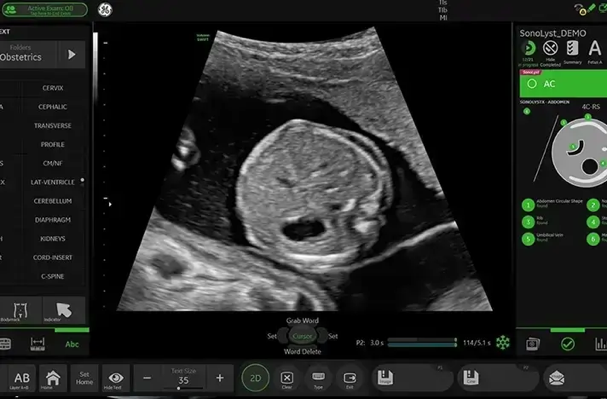

Identifica anatomía automáticamente y ayuda en etiquetado y mediciones.

Reduce interrupciones durante el examen. Menos pausas para documentar.